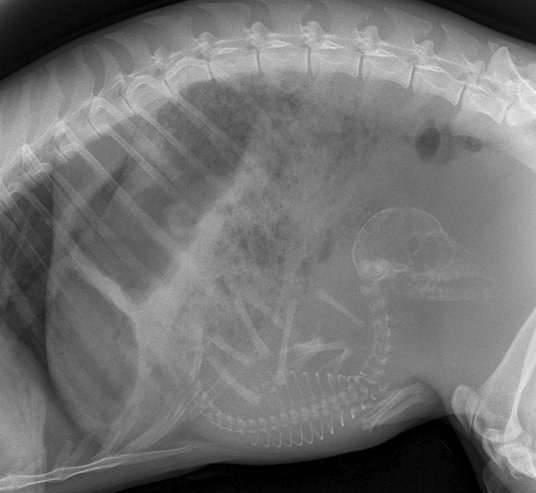

▼怀孕的狗狗